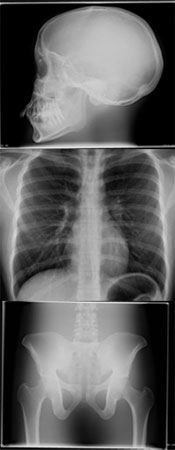

Az esetleges kóros eltérések kiderítésére használt diagnosztikai eljárás, melynek során a röntgen sugár áthatol a test megfelelő területén, s így láthatóvá válnak a problémás pontok a rtg. ernyőn vagy rtg. filmen. Általában a vizsgálatokról filmet készítenek, így a kóros eltérések részletesebben és utólag is tanulmányozhatók, a későbbiekben pedig összehasonlíthatók. A vizsgálat során a beteg mozgatása-forgatása segítségével a szervek mozgása-működése is vizsgálható. A vizsgálat néhány néhány percig tart, és a mellkasi-, hasi szervek, a csontok, a szív-érrendszer tanulmányozhatók. A kóros állapot pontos azonosítására miatt van szükség a röntgen vizsgálatokra. Bizonyos betegségek kizárása céljából a negatív lelet is fontos információ. Egészségesnek tűnő egyének biztonsági, szűrő rtg. vizsgálatára csak kis sugárterheléssel járó és egyszerűen, gyorsan kivitelezhető módszerek alkalmazhatók. A modern készülékekkel a szervezet elhanyagolható rtg. sugárnak van kitéve. Bizonyos esetekben azonban a szervezetet sugárkárosodás érheti, amely elsősorban a női és férfi ivarszerveket, másrészt a vérképzőrendszert károsíthatja. Terhességben, a magzatkárosodás nagy veszélye miatt, a rtg. vizsgálatok kerülendők.